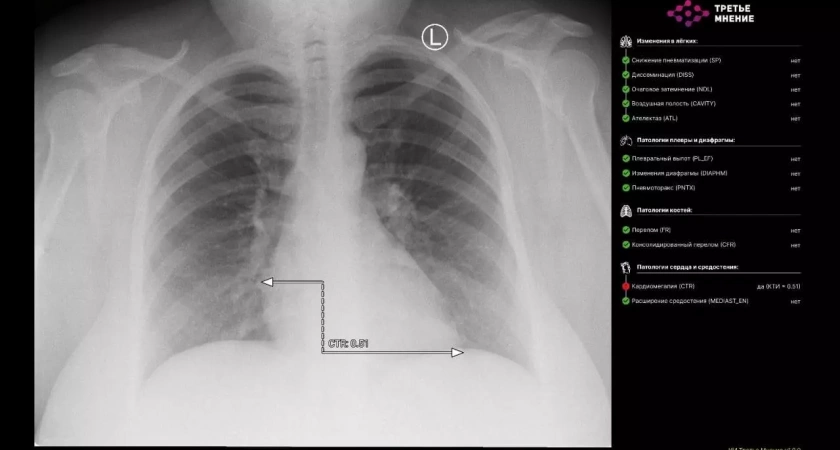

Министр здравоохранения Республики Башкортостан Айрат Рахматуллин сообщил о знаменательном событии: впервые в регионе искусственный интеллект успешно расшифровал рентгеновский снимок. Это произошло в городской больнице №21, где специалисты направили снимок органов грудной клетки на платформу «МосМедИИ».

Результат превзошел ожидания: всего за минуту цифровой помощник предоставил подробное заключение, включающее не только интерпретацию изображения, но и точную разметку патологических очагов с полным протоколом исследования.